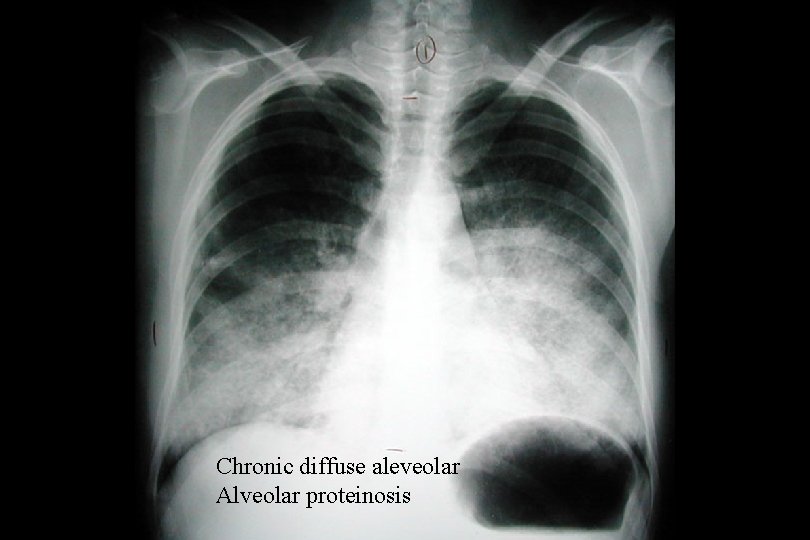

Chronic diffuse aleveolar Alveolar proteinosis